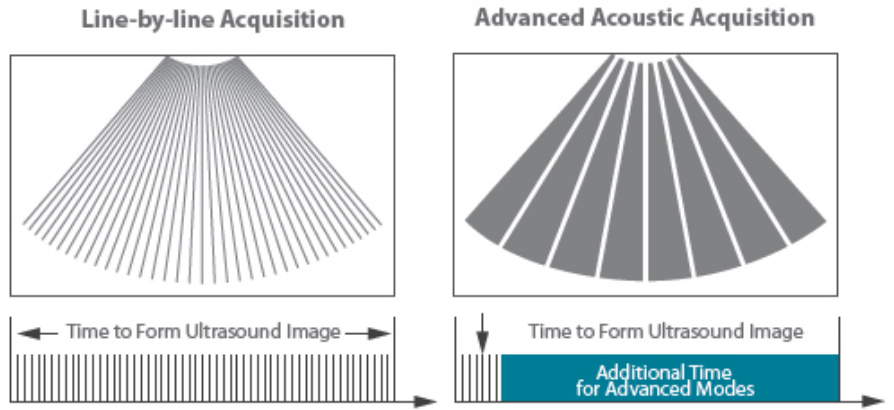

The channel data based ZST+ is an extraordinary innovation, representing an ultrasound evolution. Transforming ultrasound metrics from conventional beamforming to channel data based processing; ZST+ is able to deliver multiple imaging advances: Advanced Acoustic Acquisition, Dynamic Pixel Focusing, Sound Speed Compensation, Enhanced Channel Data Processing and Total Recall Imaging.

By transmitting and receiving a relatively smaller number of large zones, Advanced Acoustic Acquisition extracts more information from each acquisition, 10 times faster than a conventional line-by-line beamforming method.